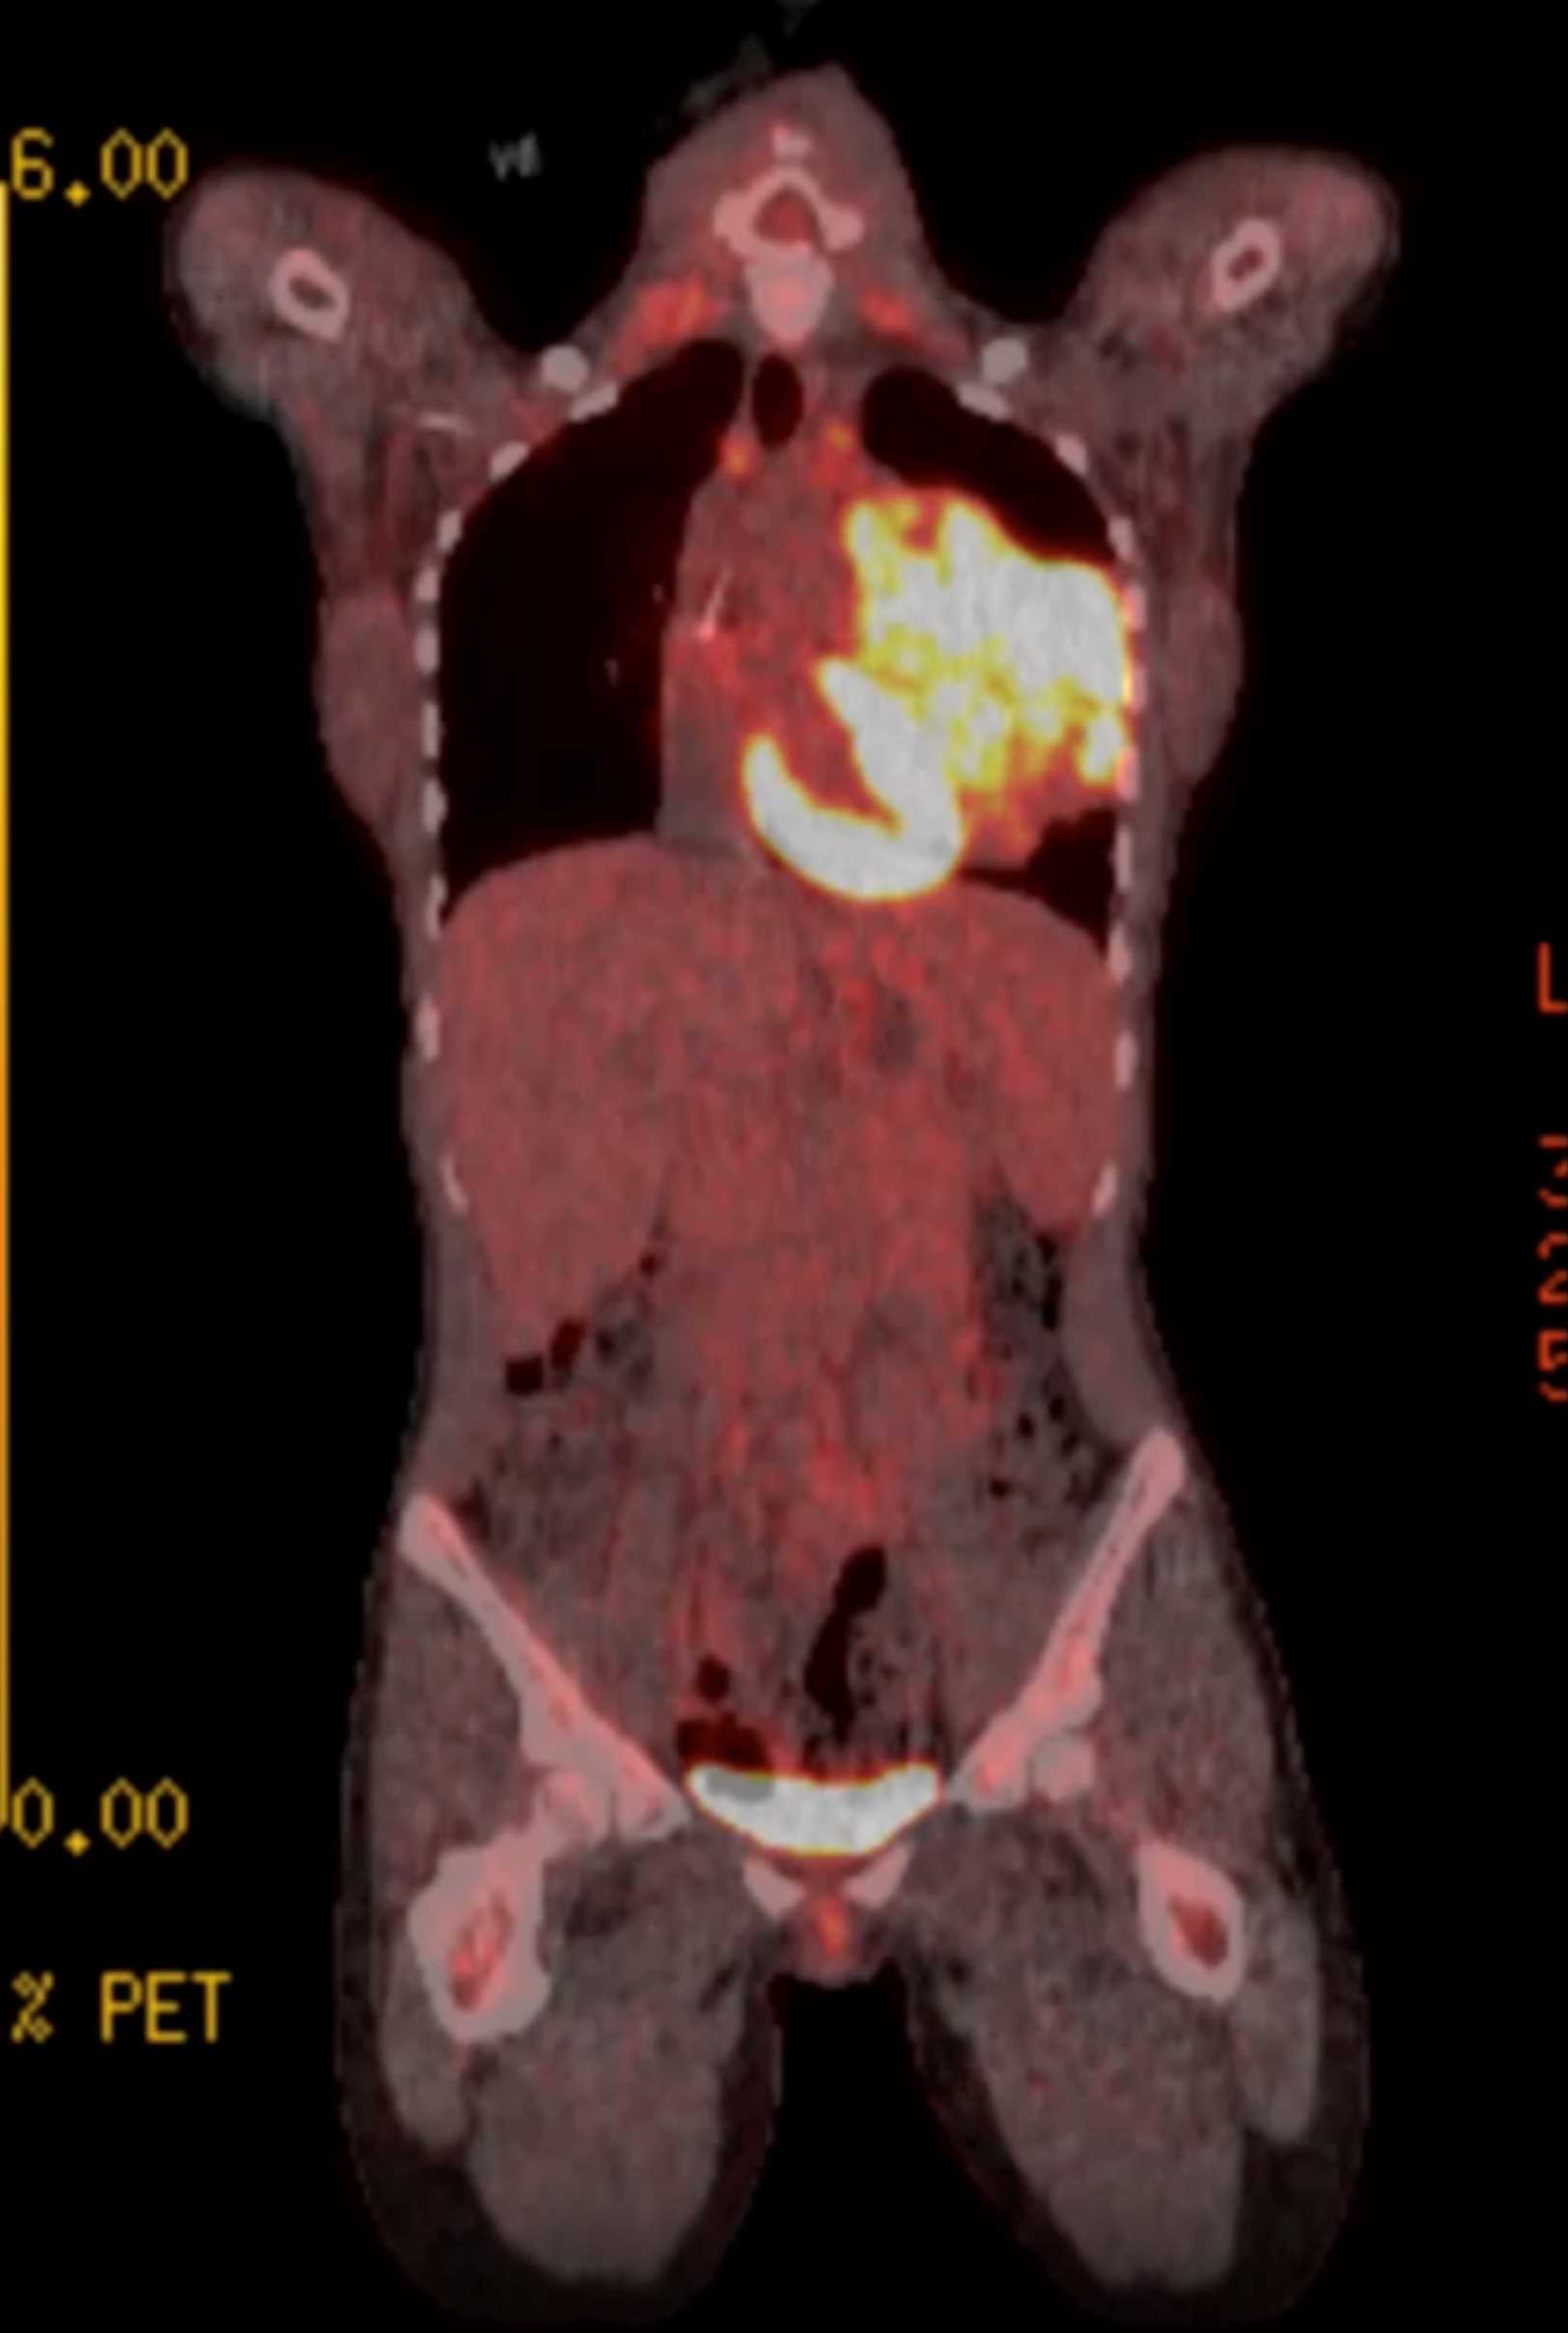

Subtle Adenocarcinoma Pancreas